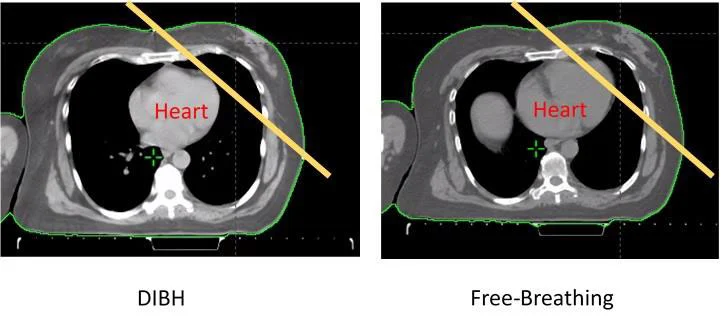

Respiratory Deep Inspiration Breath Hold (DIBH) is a specific radiation therapy technique for Breast treatment to spare doses to the heart and lungs. Using the DIBH technique, the radiation is delivered only at certain points during the patient’s breathing cycle of inspiration and expiration. The patient is asked to take a deep breath in and hold their breath for about 20 seconds.

This, in turn, will limit the amount of the heart and lung that is exposed to the radiation beam, since taking a deep breath in will allow these organs to move out of the treatment field (See sample picture of heart position completely out of the yellow line with DIBH). DIBH can be also used to minimize internal organ motion for other body sites, such as the stomach, pancreas, and liver.